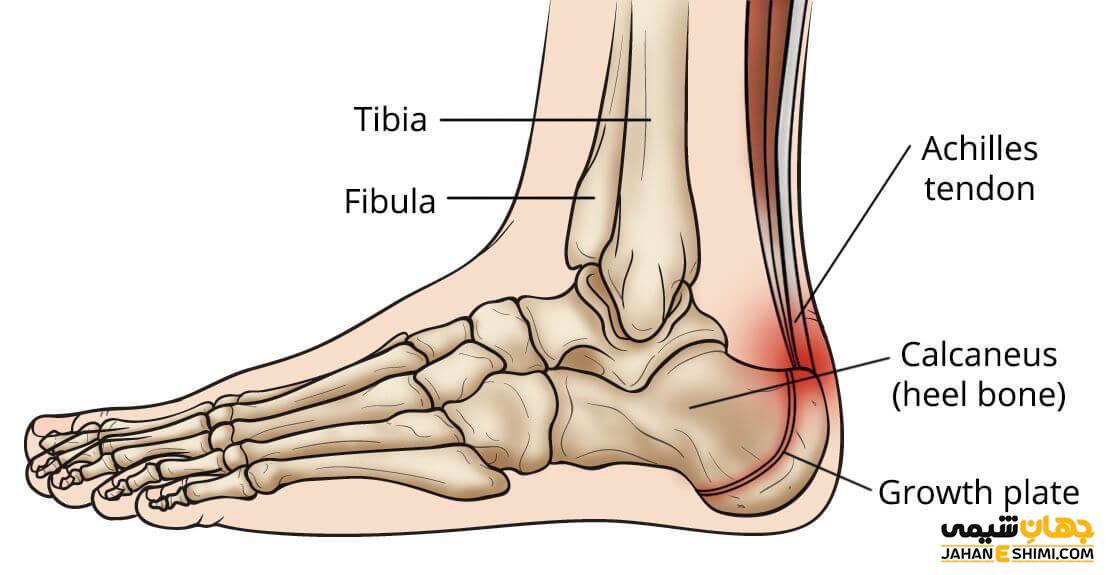

درد پاشنه یکی از شایع ترین انواع ناراحتی پا است. پاشنه که به بالشتک پای ما نیز معروف است، به طور مداوم بزرگترین حامل وزن و ضربه در ساق پا است. هر زمان که حرکت می کنیم، پاشنه های ما اولین نقطه تماس با زمین است، بنابراین حفظ ماهیچه ها و تاندون ها در یک مکان خوب بسیار مهم است.

درد پاشنه اغلب با فاشیای کف پا همراه است. تاندونیت آشیل یکی دیگر از علل درد پاشنه است. التهاب تاندون آشیل باعث درد ناشی از شکستگی و پارگی عضلات می شود. عدم انعطاف پذیری نیز یکی دیگر از علائم است.

خار پاشنه یکی دیگر از دلایل درد است. هنگامی که بافت های فاسیای کف پا تحت فشار زیادی قرار می گیرند، می تواند منجر به جدا شدن رباط ها از استخوان پاشنه شود و باعث خار پاشنه شود.

تاندونها ماهیچه های شما را به استخوان ها متصل می کنند و از مواد فیبری سخت تشکیل شده اند. آنها به عنوان نوارهای کششی عمل می کنند که به عضلات و استخوان های شما کمک می کنند در طول حرکت با هم کار کنند. بافت همبند در همه جای بدن یافت می شود، اما تاندون آشیل قوی ترین آنهاست.

تاندون آشیل در پشت ساق پا قرار دارد و ساق پا را به استخوانهای پاشنه متصل میکند و تمام وزن بدن فرد را تحمل میکنند. مشکلات تاندون می تواند از آسیب ناگهانی یا حرکت تکراری ناشی شود. اکنون می توانیم کلسترول بالا را به لیستی که تاندون های شما را در معرض خطر قرار می دهد اضافه کنیم.

علاوه بر نقش آن در تصلب شرایین، چندین مطالعه نشان دادهاند که سطوح بالای کلسترول LDL میتواند میزان تاندونوپاتی را افزایش دهد. این احتمالا به دلیل تجمع کلسترول LDL در ماتریکس خارج سلولی تاندون است. رسوبات کلسترول ممکن است منجر به تغییرات ساختاری شود که تاندون ها را ضعیف می کند. در تاندینوپاتی آشیل، تحریک تاندون ها درد شدیدی ایجاد می کند که در زمان فعالیت فرد بدتر می شود.